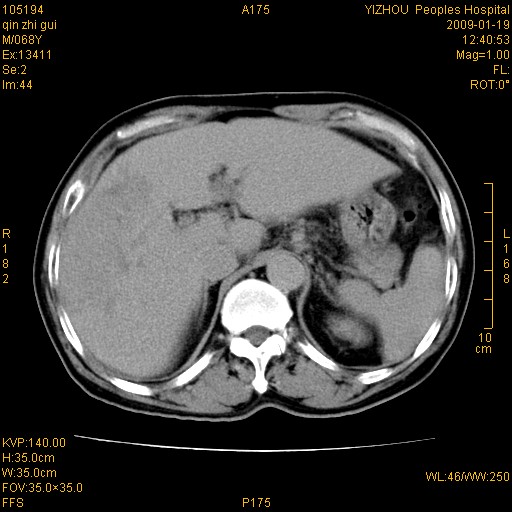

以下是引用随光逐影在2009-1-21 16:11:00的发言:[br]1)考虑肝右叶肝癌并肝静脉及门静脉瘤栓形成。2)肝硬化,少量腹水。3)胆囊炎。4)右侧少量胸腔积液。

病灶外缘凹凸不平,平扫低密度,增强动脉期有强化,门脉早显,静脉期及延期呈延迟强化,结合病史考虑右肝前叶巨块型肝癌可能性大,强化表现不除外胆管细胞癌